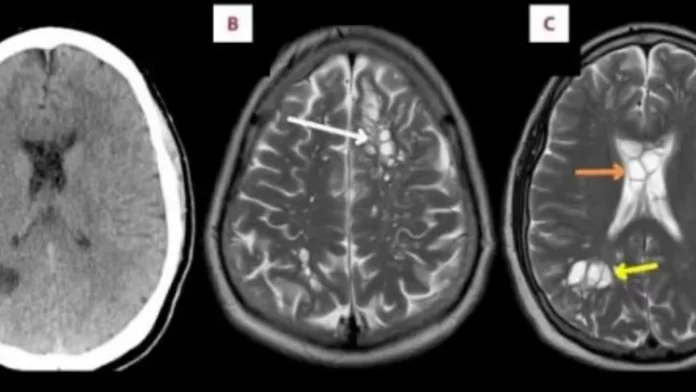

Skanimet zbuluan ciste të shumta në të dy anët e trurit të tij që rezultuan të ishin vezë të krimbit shiriti i derrit.

Vezët po i shkaktonin ënjtje nën kafkën e tij, e cila nga ana tjetër po çonte në migrenë të rregullt, sipas një raporti të shkruar nga mjekët e tij që u botua në American Journal of Case Reports.

Kur parazitët e shiritit të derrit hyjnë në tru, quhet neurocisticerkozë (NCC), thuhet në raport.